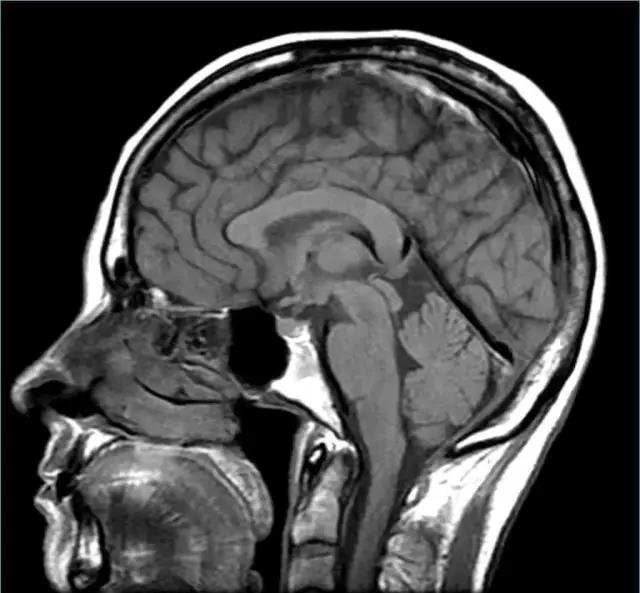

讓我們使用半球橫截面看看大腦的主要部分。因此,這是你腦袋里大腦的樣子:

現在,讓我們把大腦取出來,并刪除左半球,這讓我們能看清楚內部。

而這一整套的橫截面,讓您穿過頭去看到里面。

你的頭骨下面,又是一大堆東西,之后才是你的大腦:

讓我們使用半球橫截面看看大腦的主要部分。因此,這是你腦袋里大腦的樣子:

現在,讓我們把大腦取出來,并刪除左半球,這讓我們能看清楚內部。

fMRI使用MRI 磁共振成像技術。 MRI在20世紀70年代發明,是基于X射線的CAT掃描的演變。 MRI不是使用X射線,而是使用磁場(以及無線電波和其他信號)來產生人體和腦的圖像。

而這一整套的橫截面,讓您穿過頭去看到里面。